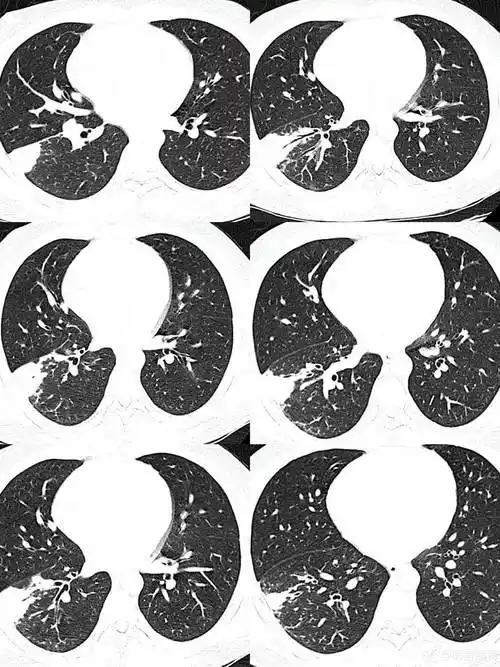

双肺下叶高密度伴充气支气管征象请分析

胸片发现:右肺中下野团片状密度增高影(实变影),内可见支气管充气征.

细支气管充气征

支气管充气征